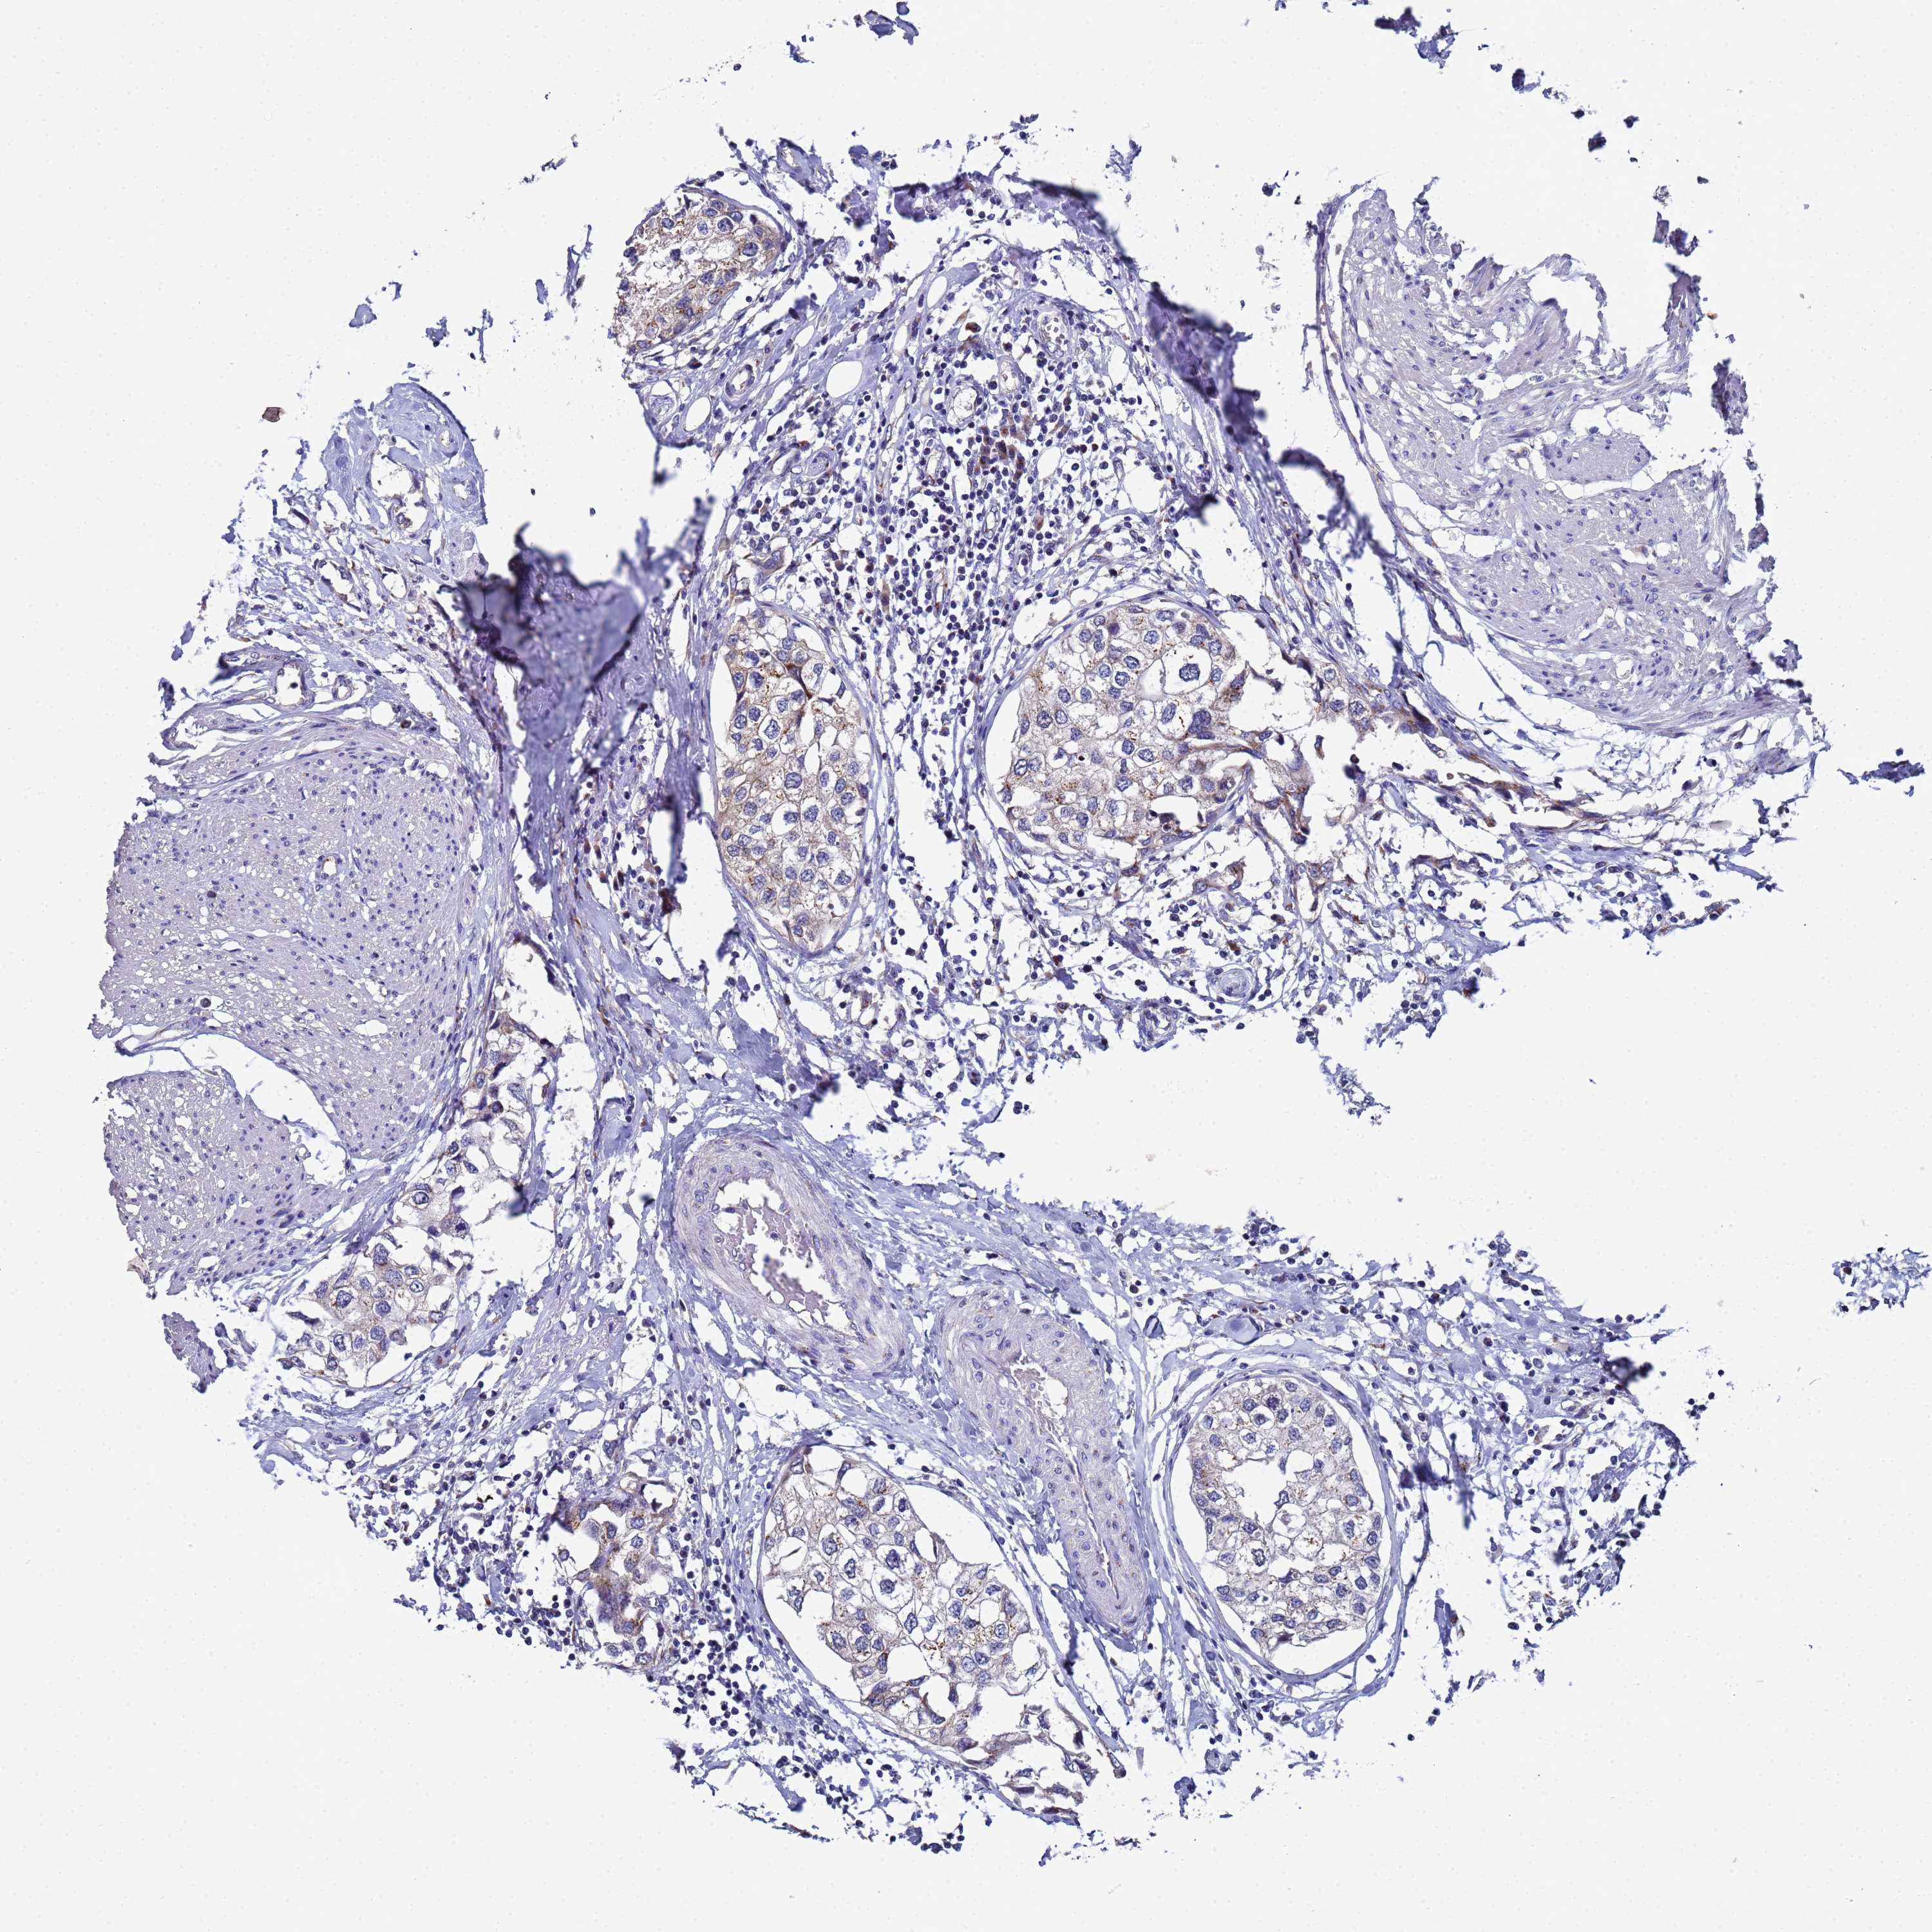

UROTHELIAL CANCER - Protein expressioni

A mouse-over function shows sample information and annotation data. Click on an image to view it in a full screen mode. Samples can be filtered based on level of antibody staining by selecting one or several of the following categories: high, medium, low and not detected. The assay and annotation is described here.

Note that samples used for immunohistochemistry by the Human Protein Atlas do not correspond to samples in the TCGA dataset.

Antibody stainingi

Antibody staining in the annotated cell types in the current human tissue is reported as not detected, low, medium, or high, based on conventional immunohistochemistry profiling in selected tissues. This score is based on the combination of the staining intensity and fraction of stained cells.

Each image is clickable and will lead to virtual microscopy that enables deeper exploration of all samples and also displays staining intensity scores, fraction scores and subcellular localization as well as patient and tissue information for each sample.

Antibody HPA045902

Staining

High

Medium

Low

Not detected

Intensity

Strong

Moderate

Weak

Negative

Quantity

>75%

75%-25%

<25%

None

Location

Nuclear

Cytoplasmic/membranous

Cytoplasmic/membranous,nuclear

Urothelial carcinoma, High grade

Urothelial carcinoma, Low grade